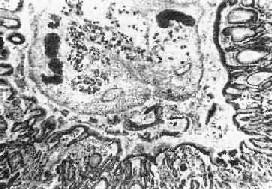

1.肝 肉眼观,肝轻度肿大,尤以左叶为著,严重时在左叶被膜下即可见到因成虫机械阻塞而扩张的胆管分支,可能因左叶胆管较平直,易被童虫侵入之故。切面见肝内大、中胆管呈不同程度扩张和管壁增厚,胆管的直径可达3~6mm,壁可厚达0.5~3mm(图19-12)。胆管腔内充满胆汁,并含有数目不等的成虫。华支睾吸虫前端较细,后端钝圆,形似葵瓜子,虫体长约10~25mm,宽约3~5mm,柔软而半透明。在有大量虫体寄生的病例,解剖时轻压肝脏,即可见成虫由各胆管中鱼贯而出。镜下,根据感染虫数和感染持续时间的不同,病变可轻重不等。肝内胆管扩和,胆管上皮细胞呈不同程度增生,严重者上皮向管腔内呈乳头状增生,并可在粘膜下见多量的增生腺体,形成腺样结构(图19-13)。上皮细胞还常发生杯状细胞化生而分泌大量粘液。管壁有不等量淋巴细胞、浆细胞和嗜酸性粒细胞浸润。慢性病例则伴有明显的纤维结缔组织增生。部分病例汇管区的结缔组织也呈轻度增生,伴有上述炎性细胞浸润。在急性反应时汇管区的小胆管周围也可有多量嗜酸性粒细胞浸润,而肝实质细胞一般无明显改变。

图19-13 肝华支睾吸虫病

胆管内可见虫体,胆管粘膜有腺样增生及炎症